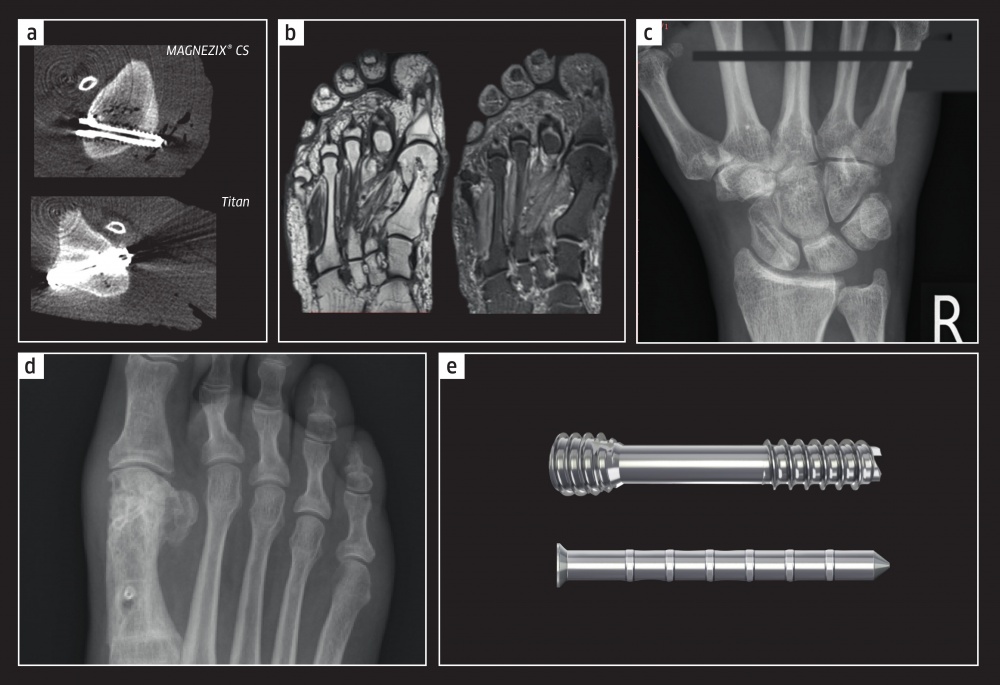

Als nicht resorbierbare metallische Osteosynthesematerialien werden hauptsächlich Titan und Stahl eingesetzt. Gegenüber Knochen weisen diese Metalle eine sehr viel höhere Steifigkeit auf, was eine Belastungsabschirmung (Stress Shielding) bewirken kann. Durch die Inaktivierung des Knochenstoffwechsels in der Frakturzone wird das Remodeling behindert, was in einer Osteoporose resultieren kann. Permanente Implantate aus Titan oder Stahl erzeugen zudem Artefakte in der radiologischen Bildgebung, insbesondere im CT. Für die MRT sind sie gänzlich ungeeignet. Generell können Implantate im Körper Fremdkörperreaktionen und Allergien hervorrufen.

Abb. 1b: MRT-Schichten eines rechten Fußes ca. drei Jahre nach Chevron-Osteotomie bei Hallux valgus: deutlich erkennbare Verdichtung in der vorherigen Implantat-Zone i.S. eines Umbaus zu körpereigenem Knochengewebe.

Abb. 1c: Scaphoid-Fraktur, versorgt mit einer MAGNEZIX® CS 3.2 (a.p.-Aufnahme rechte Hand): knöcherne Durchbauung bei residualen Aufhellungen um das Implantat.

Abb. 1d: Patientin nach Chevron Osteotomie mit zwei MAGNEZIXR CS 3.2 bei Hallux valgus, sechs Monate postop. (belastete a. p.-Aufnahme rechter Fuß).

Abb. 1e: MAGNEZIX® CS (o) und eines MAGNEZIX® Pin (u). (Bilder: Medizinische Hochschule – MHH, Hannover

(1a, 1b); Dr. U. Schachinger, Regensburg (1c); T. Juutilainen., Helsinki (1d)

Werkstoffe aus Magnesium in Form verschiedener Legierungen stehen schon seit der Jahrtausendwende im Fokus der biomedizinischen Forschung. Ein klinischer Erfolg zeichnete sich in diesem Zusammenhang allerdings nur in Studien mit Koronar-Stents ab. Es gab aber gute Gründe, über einen Einsatz von Magnesium in der orthopädischen Chirurgie nachzudenken: Ein Implantat aus diesem Werkstoff würde mit der Stabilität eines herkömmlichen metallischen Implantates aus Titan oder Stahl vergleichbar sein, sich aber gleichzeitig auflösen. Magnesium-basierte Implantate bieten darüber hinaus den Vorteil einer sehr guten Kompatibilität mit den Methoden der CT- (Abb. 1a), und MRT-Bildgebung weshalb nur geringe Bildartefakte und eine gute Sichtbarkeit resultieren. Zu Beginn des 19. Jahrhunderts wurde Magnesium bereits experimentell als resorbierbares NahtMaterial verwendet. Ebenso begann man, erste Versuche in den Bereichen von Osteosynthese, Gelenkplastiken und in der Gefäßchirurgie mit Magnesium als Draht durchzuführen. Initial zeigten sich bei diesen frühen Studien sehr gute Resultate. Die häufig zu rasch ablaufende Korrosion des Magnesiums führte jedoch später häufig zu Komplikationen, weshalb der Werkstoff für Implantationsvorhaben zunächst unattraktiv erschien. Erst zu Beginn des 21. Jahrhunderts wurden Magnesium und seine Legierungen erneut für Anwendungen im Bereich der Osteosynthese in Erwägung gezogen. Gegenüber den in der Medizin etablierten Polymerwerkstoffen weisen resorbierbare Implantatmaterialien auf Magnesiumbasis eine gute Biokompatibilität sowohl in vitro als auch in vivo auf. Als deutlicher Vorteil gegenüber Polymeren erweist sich jedoch die in der Regel wesentlich höhere Festigkeit der Magnesiumwerkstoffe, die ihre Erschließung für den medizinischen Sektor derzeit so attraktiv macht. Magnesium zeigt beispielsweise gegenüber Bio-Keramiken und Polymeren ein für viele Implantationsanwendungen erheblich geeigneteres Verhältnis aus mechanischer Festigkeit und Duktilität. Die noch im 19. Jahrhundert als unkontrollierbar geltenden Korrosionseigenschaften des Magnesiums können inzwischen durch optimierte Herstellprozesse (z. B. Strangpressen) sowie durch die Verwendung hochentwickelter Legierungs- und Beschichtungssysteme gezielt ausgelegt und steuerbar gemacht werden. So finden sich in den letzten Jahren zahlreiche in vitro- und auch in vivo-Untersuchungen zur Verwendbarkeit von Magnesiumlegierungen in der Biomedizintechnik.

Klinisch wurden bislang in fast allen Fällen (weit über 7 000) positive Resultate erzielt. Umfangreiche Vigilanzdaten zeigen in nahezu allen Fällen eine regelhafte knöcherne Ausheilung der nach Osteotomie oder Fraktur verschraubten Knochen. Bisherige Schwierigkeiten im Umgang mit dem Implantat oder unerwünschte klinische Ergebnisse waren vorwiegend auf eine unscharfe Indikationsstellung oder eine mangelhafte OP-Technik zurückzuführen (Seitz et al., 2015). In manchen Fällen treten im Röntgenbild mehr oder minder stark ausgeprägte Aufhellungszonen um das Implantat herum auf. Dieses Phänomen ist dem Abbau der Implantate durch Degradation geschuldet (Knochenumbauzone). Die MRT-Befunde nach drei Jahren Follow up zeigen eindeutig den Umbau der Schraube in kortikalis-ähnliches, körpereigenes Knochengewebe (Abb. 1b). Auch wenn die klassische Herbert-Schraube ihre primäre Indikation bei der Skaphoid-Fraktur hat (Abb. 1c), so ist das weltweit erste metallische bioabsorbierbare Implantat, die MAGNEZIX® Compression Screw (CS), bereits in den verschiedensten Körperregionen eingesetzt worden, u.a. bei den folgenden Indikationen: Hallux valgus (Abb. 1d), Klaviculafraktur, proximale Radiusfraktur (Radiusköpfchen), Unterarmfraktur, distale Radiusfraktur, Metakarpalefrakturen, Azetabulumfrakturen, Hüftkopffrakturen (Pipken), distale Femurfraktur, Patellafrakturen, Innen- und Außenknöchelfrakturen u. a. m.